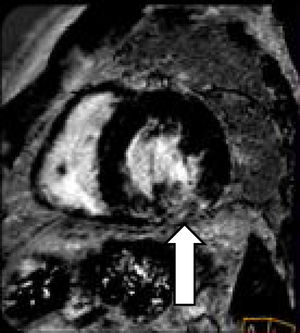

Observación clínicaUn varón de 48 años, sin hábitos tóxicos ni antecedentes de interés ingresa por cefalea, parestesias en la extremidad superior derecha y crisis hipertensiva. TC craneal: sin alteraciones. Se inicia tratamiento vasodilatador, diurético y antiagregante plaquetario con buen control de las cifras tensionales y desaparición de la focalidad neurológica. En la RX de tórax se aprecia redistribución vascular e hilio derecho aumentado de tamaño. Se realiza TC toracoabdominal que muestra múltiples adenopatías de tamaño valorable, entre 10 y 20mm a nivel intratorácico (en el espacio prevascular, subcarinales, pretraqueales derechas, hiliares bilaterales y adyacentes a bronquio inferior izquierdo), sin alteraciones en el parénquima pulmonar ni a nivel abdominal. Se practica broncoscopia, sin alteraciones, y 3 PAAF ganglionares con abundante celularidad linfoide sin atipias. Las baciloscopias y el cultivo para micobacterias resultan negativos. Un ecocardiograma transtorácico muestra: ventrículo izquierdo con moderada dilatación de su cavidad, ligera hipertrofia concéntrica y moderada reducción de su contractilidad global por acinesia inferior e hipocinesia del resto de segmentos. FE estimada 37%. Disfunción diastólica de tipo restrictivo sugestiva de aumento de presión capilar. Moderada dilatación de la aurícula izquierda. La cardiorresonancia magnética (CRM) muestra:

Patrón parcheado intramiocárdico ediobasal inferolateral y basal inferior y lateral del ventrículo izquierdo sin necrosis, sugerente de sarcoidosis versus enfermedad de Fabry (fig. 1).

Se cursa una muestra de gota seca (blood-spot) que descarta enfermedad de Fabry, y se realiza nueva PAAF ganglionar, por ecobroncoscopia, que muestra material hemático y linfocitos sin atipias ni granulomas. Las baciloscopias y el cultivo para micobacterias fueron negativos. Una coronariografía no objetiva lesiones angiográficas significativas. Una gammagrafía con galio muestra captación en la región mediastínica alta anterior derecha e izquierda, que orienta hacia un origen inflamatorio, sin descartar un proceso linfoproliferativo. La analítica general, incluida la determinación de inmunoglobulinas totales, enzima conversora de la angiotensina, determinación de autoanticuerpos y serologías viricas resultaron negativas o normales.